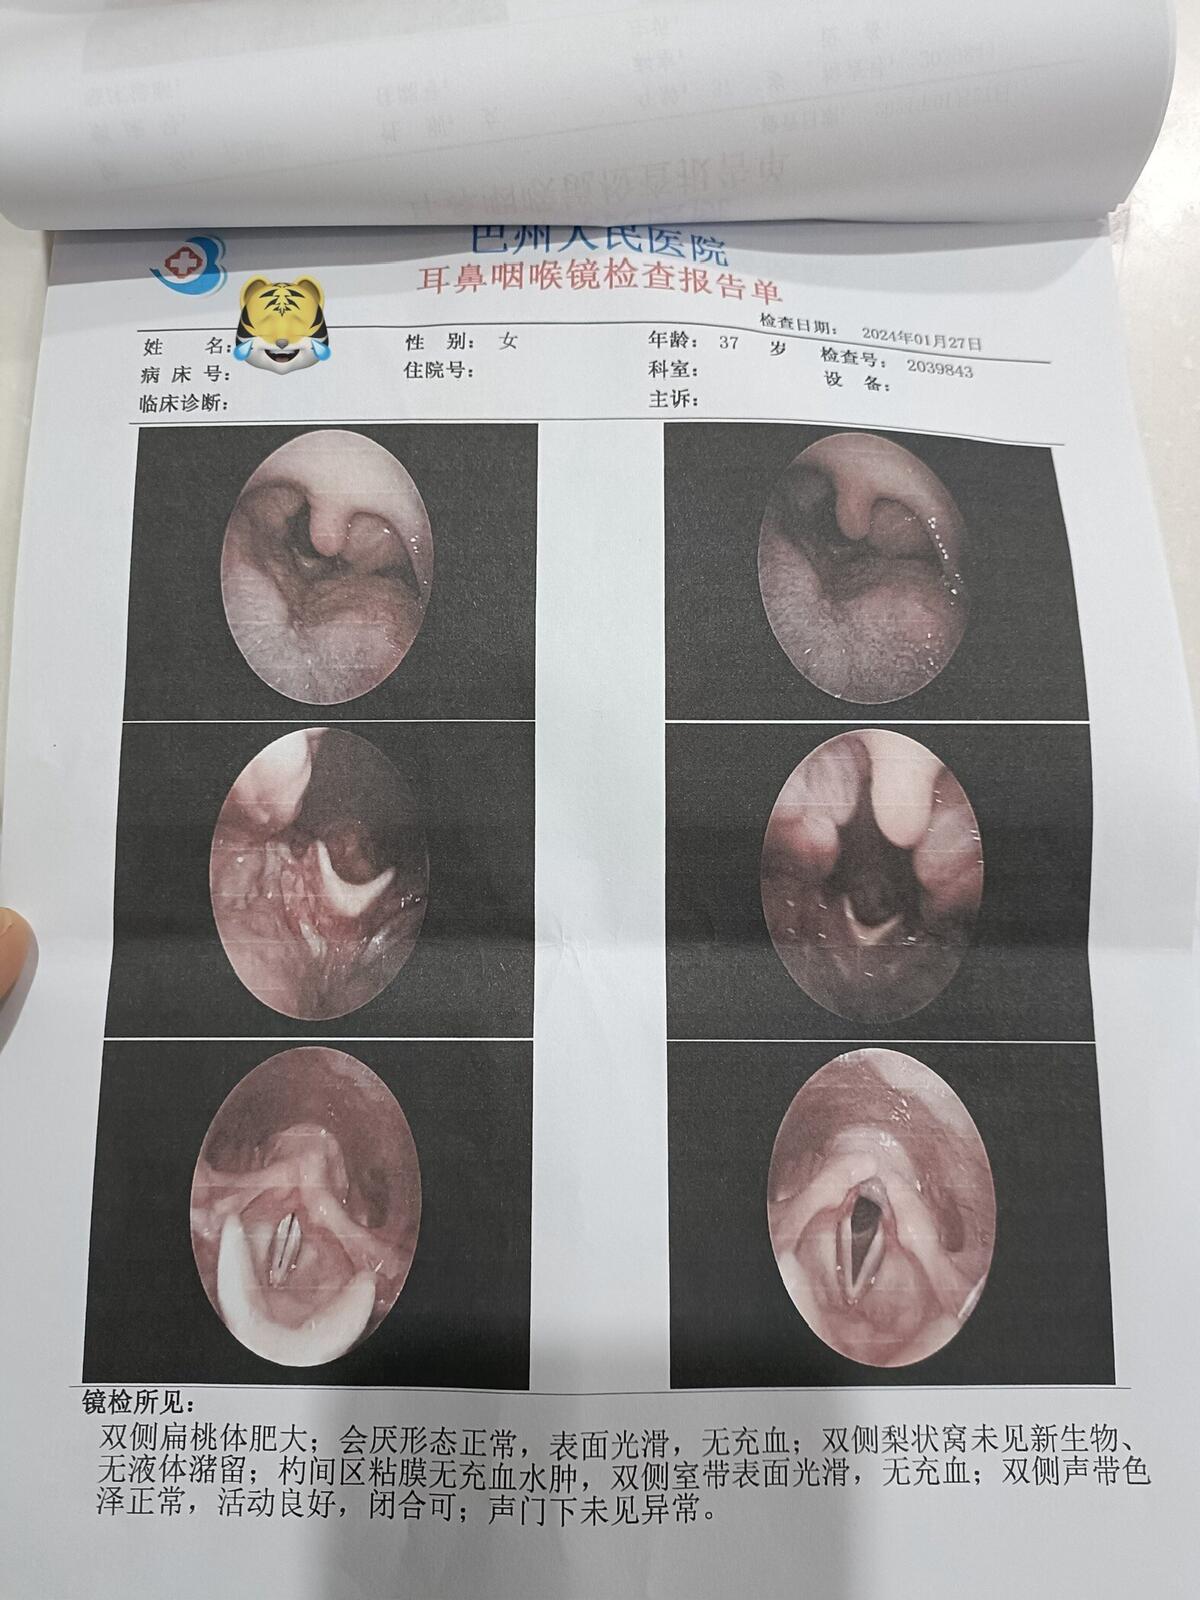

之前同一天做过“鼾症兄弟”、“鼾症兄妹”和“鼾症父女”,这是第一次给“鼾症母女”同一天手术。这对母女来自新疆巴音郭楞,重度鼾症父亲37岁,因为扁桃体肥大,自小打鼾,4年前产后打鼾加重,伴夜间憋醒,严重影响睡眠,当地医生建议患者戴呼吸机,但是她无法耐受呼吸机。电话咨询后,下定决心来广州找我手术。同时她也把4岁女儿打鼾和张口呼吸的情况也详细告诉我,鼾症女儿因为扁桃体3度肥大,腺样体堵塞后鼻孔2/3,造成张口呼吸,对于这样的孩子,一定需要早点手术干预,不然会影响面部发育和生长发育,甚至智力发育。所以我就让她们母女一起来广州找我手术。手术时发现母女俩的扁桃体肥大,因为女孩子4岁,我常规保留双下极扁桃体的1/5和腺样体的1/5。希望母女手术后身体早日恢复正常!有一个安稳的睡眠质量,健健康康的生活!

肥大扁桃体